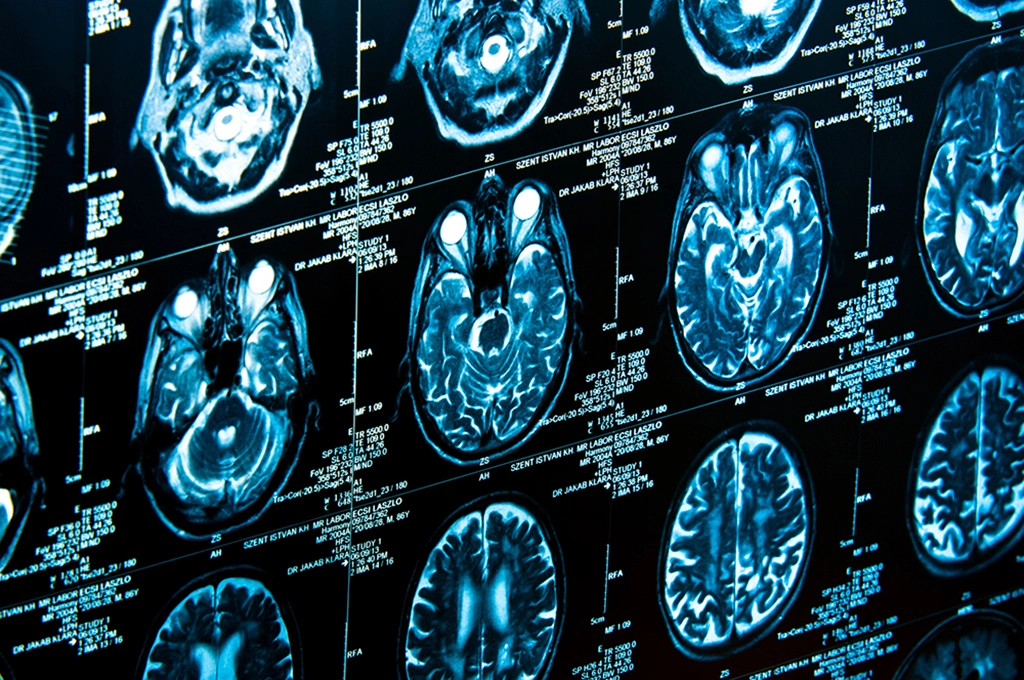

Unfortunately, getting the right, unbiased advice in that stressful moment is often far from reality. Today’s corporate hospital culture and profit-driven treatment protocols frequently push us to authorize an immediate CT scan for our little ones. Putting a few-months-old infant inside a huge, monstrous machine makes our hearts skip a beat, and it naturally forces us to question: Do we really require this CT scan to rule out a head injury? Is there any other way to find out?